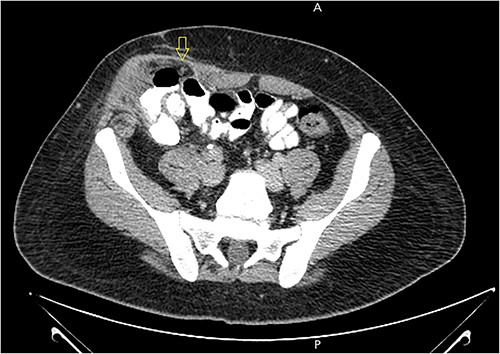

A 21-year-old male patient, obese with BMI of 35, known case of incisional hernia that occurred after an open appendectomy one year ago, was admitted to the emergency department complaining of acute abdominal pain for one-day duration. The pain was localized to the RLQ at the site of the incisional hernia, sudden in onset, sharp in character, not radiated with no known aggravating or relieving factors, and not associated with nausea, vomiting, abdominal distention, or change in bowel habit. On admission, he had normal vital signs. Physical examination showed a huge reducible incisional hernia in the RLQ area, at the McBurney scar with no signs of inflammation. There was significant tenderness at the McBurney point. Laboratory tests showed an increase in C-reactive protein (CRP) 180.00 g/l (0–5 g/l) and leukocyte count 17 000*109/L (4.3–10.8 × 109/L). Other Laboratory tests are all within normal. Abdomen CT scan with IV contrast (Fig. 1) demonstrated a large peritoneal defect containing cecum and terminal ileum associated with adjacent facial thickening, prominent lymph nodes, fat stranding, and 1.5*2 cm fatty density, no signs of bowel obstruction. The initial diagnosis consists of EA or early incarcerated hernia. Nasogastric decompression was done, and IV fluids and antibiotics were started. However, the pain gradually increased despite medical management. Because of the severity of the abdominal pain, a decision to proceed with surgical exploration was made. Under general anesthesia, a McBurney incision was done at the site of the incisional hernia. Intraoperatively (Fig. 2), a hernia sac was identified, and multiple aggregated gangrenous EA infarctions were excised (Fig. 3), then a hernioplasty was used to repair the hernial defect. The postoperative period was uneventful. The patient started a soft diet on Day 2 and was discharged from the hospital on Day 4. Histopathologic examination showed an aggregate of fatty-fibrous tissue with fat necrosis, surrounded by active inflammation confirming the diagnosis of EA.

Abdomen CT scan with IV contrast demonstrated a large m peritoneal defect containing cecum and terminal ileum with an oval fatty density 1.5*2 cm represent an inflamed epiploic appendages (arrow) that have a hyper-attenuating rim and “central dot sign” with inflammatory changes in the adjacent fat tissue.